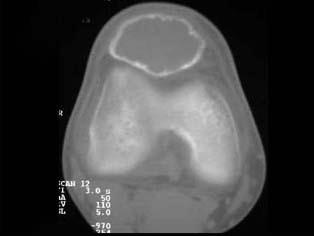

问题 患者,男性,30岁,近2年来感右膝疼痛,活动后加重,2周前由于剧烈运动后,右膝活动受限,右膝压痛明显,有波动感,皮肤稍显红肿,以髌骨部明显,请结合所提供图像,选择最佳选项 ( )

选项 A、骨巨细胞瘤 B、动脉瘤样骨囊肿 C、非骨化性纤维瘤 D、骨囊肿 E、纤维性骨皮质缺损

答案 B